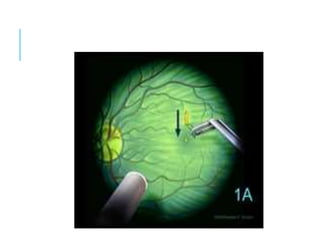

1A impending hole: Yellow spot

1B occult hole: yellow ring

Source of image: AAO, Text Yanoff,

STAGE 1 (IVTS: VMT) Typicallyasymptomatic Loss of foveal depression 1A impending hole: Yellow spot 1B occult hole: yellow ring 50% resolved spontaneously 50% progress to stage 2 VMT: Perifoveal PVD (3mm) with retinal changes on OCT Associatons: AMD, RVO,DR No true retinal defect present, PR layer is intact, No vitreofoveal separation Oblique Vitreofoveal traction is responsible Source of image: AAO, Text Yanoff,